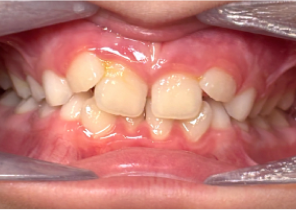

Opis przypadku nr 2

7 lat, 11 miesięcy, 24 etapy leczenia Invisalign® Palatal Expanders

Dzięki uprzejmości dr. Davida R. Boschkena

Przed ekspansją eInvisalign Palatal Expander

Po ekspansji Invisalign Palatal Expander

Po leczenie Invisalign Palatal Expander